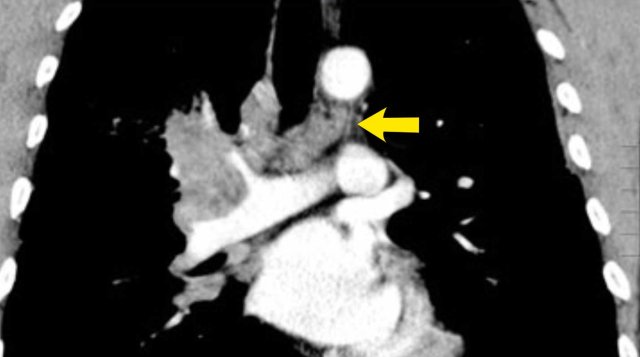

N2 Nodes

N2-nodes represent ipsilateral mediastinal or subcarinal lymphadenopathy.

• N2a - Single N2 station involvement

• N2b - Multiple N2 station involvement

Image

Right sided tumor with lymph node metastases in multiple (4R and 2R) ipsilateral mediastinal stations (N2b).